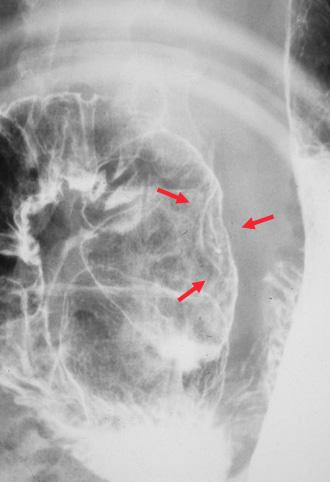

A case of ectopic gastric mucosa in the duodenal bulb which showed IIa+IIc type tumor like appearance.

Tumor-like lesions/ectopic mucosa

Duodenum/First portion, bulb

X-ray

15 - 19